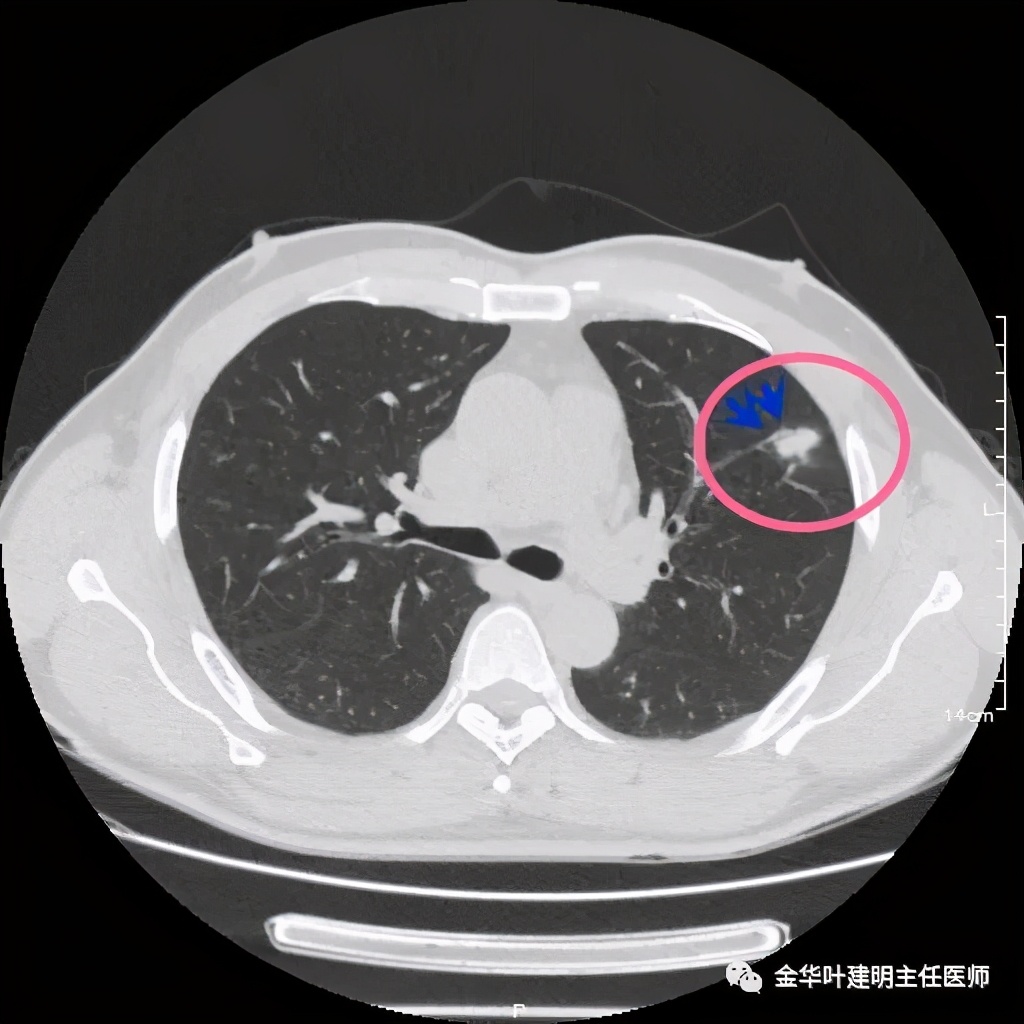

紫色箭头示病灶的边缘向内凹陷,说明无膨胀性,绿色示晕征,粉色箭头指向病灶

此层面示病灶呈三角形,缺乏膨胀性,边缘较直,没有毛刺征,实性部分没有收缩纠集感,绿色箭头示晕征

实性部分我看是有所缩小改善的,边上磨玻璃样的晕征更加明显了点

上图示病灶边缘向内凹陷,同时仍伴晕征

上图红色箭头示仍有血管进入,但蓝色箭头示边缘内凹,绿色示仍有晕征

上图红色箭头示血管进入病灶